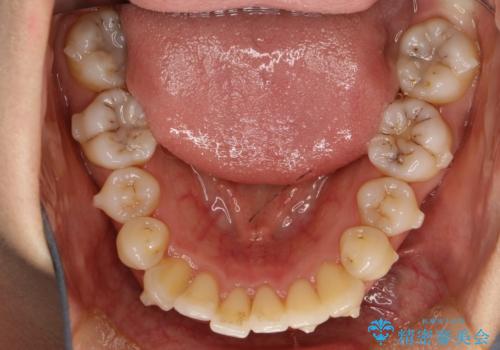

前歯が前後反対にかんでいる インビザラインによる目立たない矯正

- 前歯のかみ合わせを主訴に来院されました。

なるべく目立たずに矯正をしたいとのことで、インビザラインで矯正をすることとしました。

歯と歯の間をわずかに削り、ガタガタを改善しました。